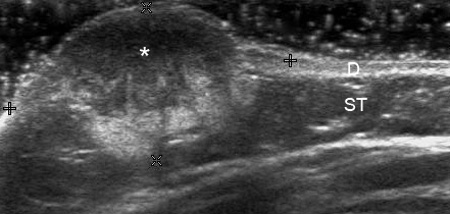

Диагностика гемангиом производится на основании расспроса о времени появления опухоли, данных объективного осмотра, при необходимости выполняются дополнительные исследования, такие как допплерография, МРТ, компьютерная томография.

Для выяснения состояния гемангиомы (пролиферация или регресс) изучаются различные клеточные маркеры (фактор роста фибробластов, фактор роста эндотелия сосудов, тканевой ингибитор металлопротеиназ и другие). В некоторых случаях наличие гемангиомы является лишь одним из проявлений врожденных синдромов. Правильный диагноз во многом определяет успех лечения пациента. Лечебная тактика зависит от локализации гемангиомы и темпа ее роста.